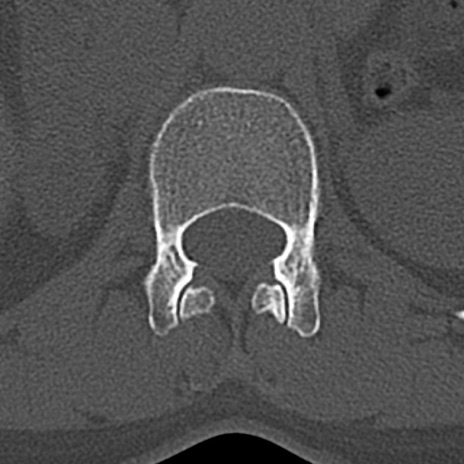

腰椎CT

横断像と矢状断像